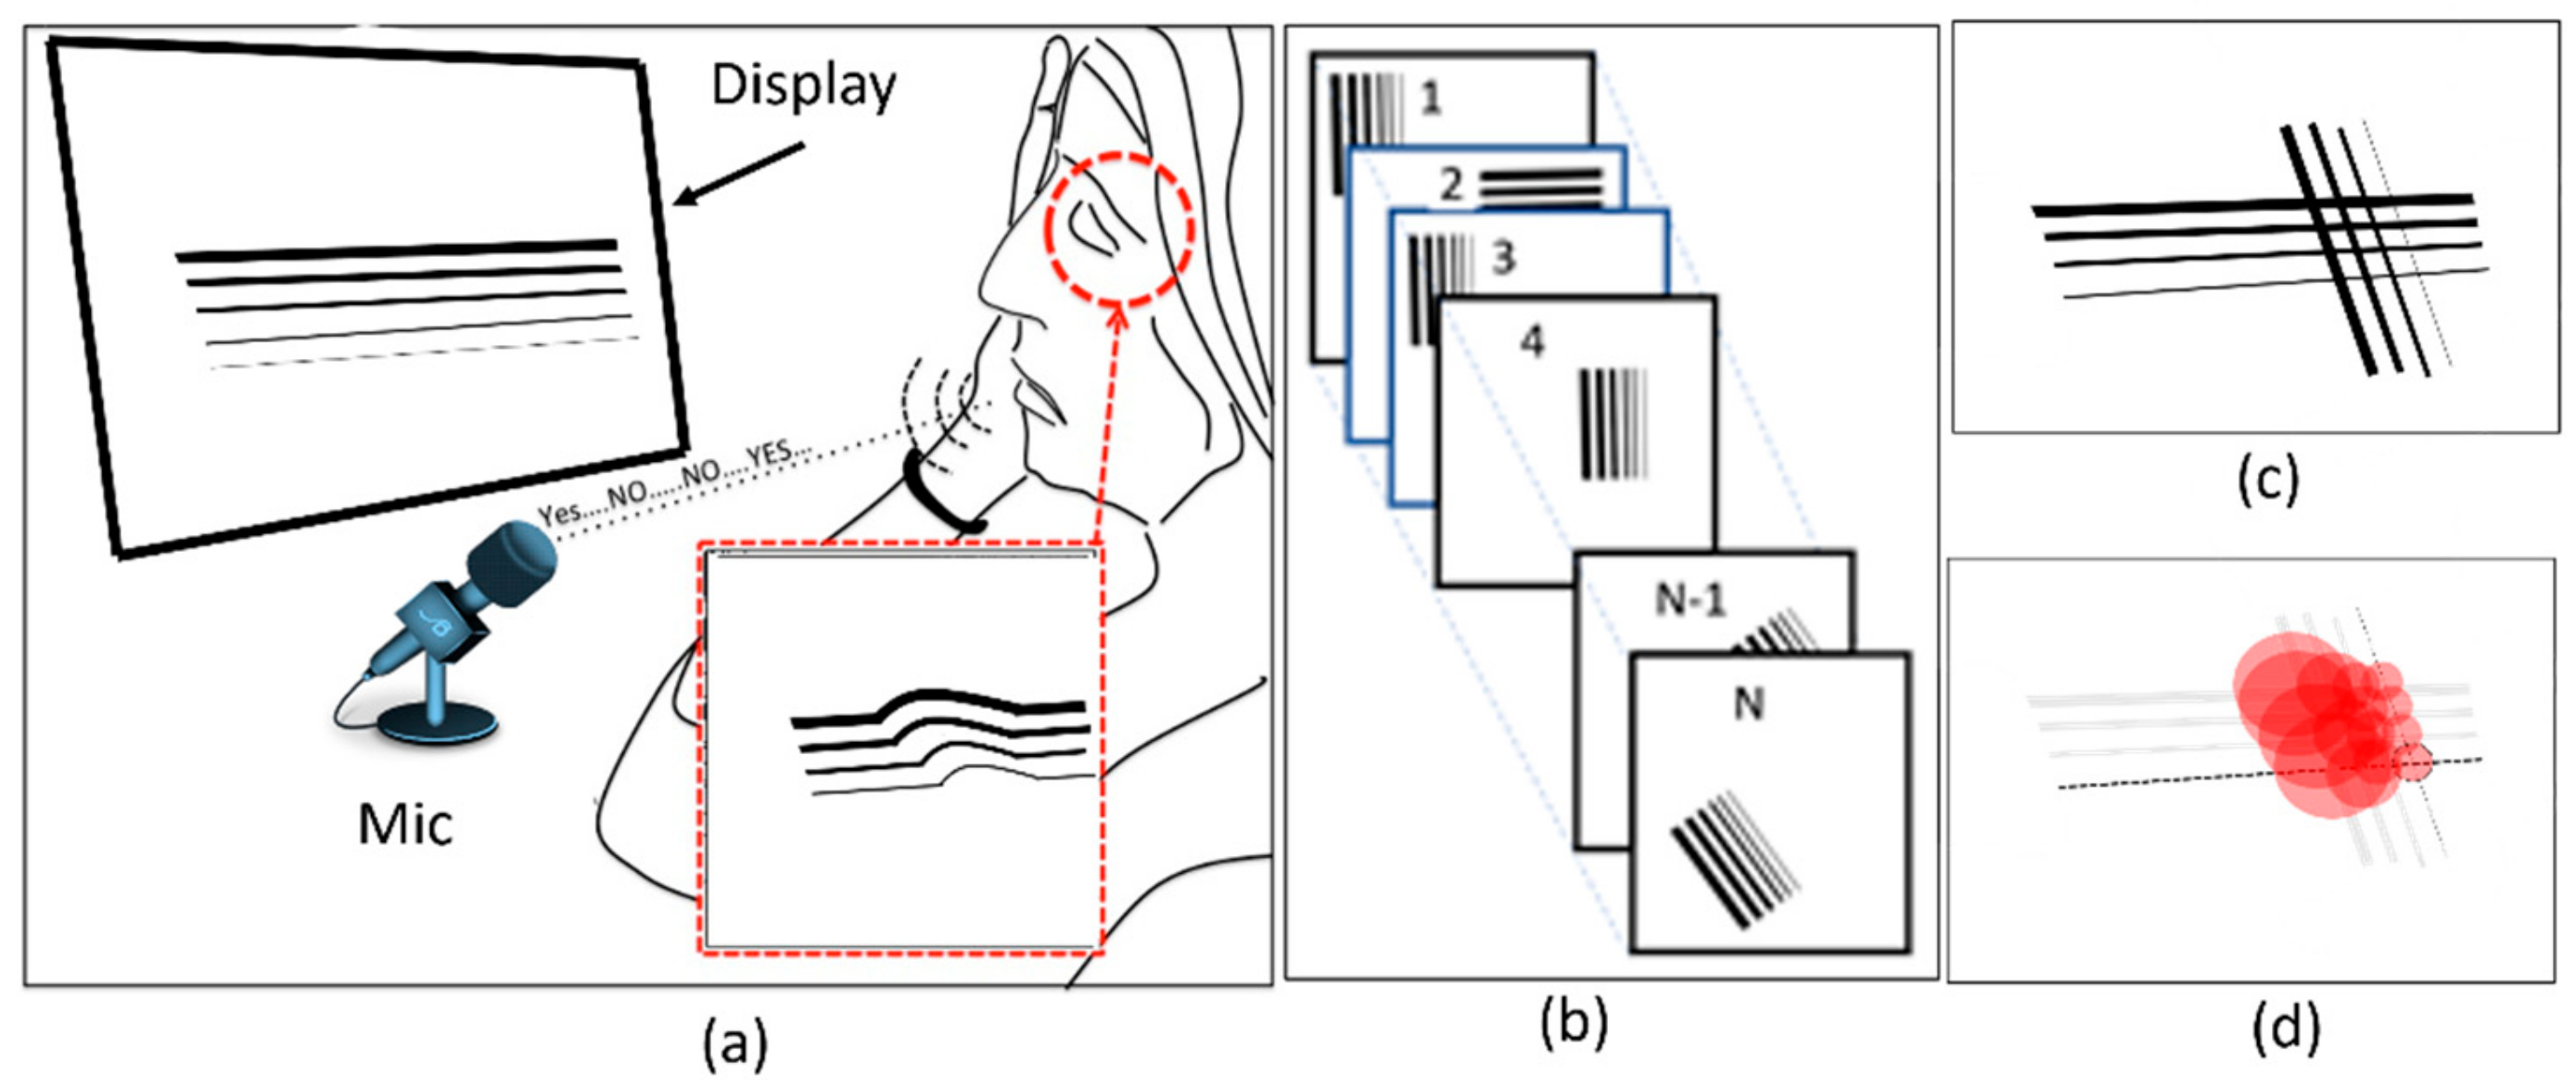

4. Proposed Method and Platform

4.1. Hardware Development

4.2. Software Development

4.2.1. NGRID VD Test and SVG VD Test Editor

4.3. Heatmap Generator

5.2. Visual Distortion Test

5.3. Estimation of Visual Distortion